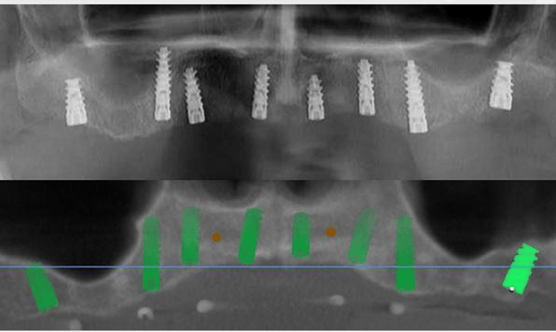

Let's look at a real case: A patient presented with limited mesial-distal space for implant placement. Using Alpha-Bio Tec's guided surgery system, we achieved:

- Perfect implant positioning

- No damage to adjacent tooth roots

- Ideal prosthetic orientation

- Advanced CT scanning protocols (including innovative Dual Scan technology)

- Precise 3D printing capabilities

- Specialized surgical kits with integrated depth control

- Comprehensive planning software